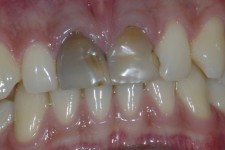

Dentalna protetika - krunice, mostovi, proteze

Vrhunska optička estetska i mehanička svojstva bezmetalnih keramičkih radova